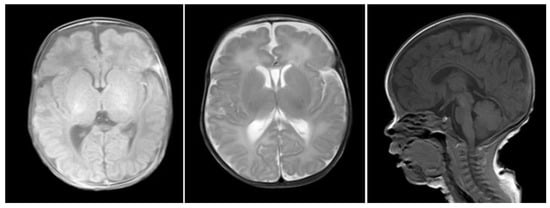

2. Case Report

2.1. Clinical Data